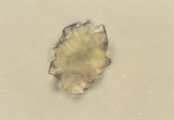

ЦИСТИНОВАЯ КРИСТАЛЛУРИЯ

Особенности

Цистиновые кристаллы бесцветные, характерной гексагональной формы с равными или неравными сторонами (рис. 25-26). Они могут появляться одиночно, но чаще в виде агрегатов. Их определение требует уменьшения световой интенсивности, так как они тонкие. Цистиновые кристаллы чаще всего формируются в концентрированной кислой моче. Формирование явной щелочной мочи, как следствие инфекции или контаминации уреазообразующими микробами, может способствовать образованию цистиновых кристаллов. Добавление ледяной уксусной кислоты после замораживания и центрифугирования может улучшить определение типичных кристаллов в образцах щелочной мочи. Цистиновые кристаллы нерастворимы в уксусной кислоте, спирте, ацетоне, эфире и кипящей воде. Они растворимы в аммиаке и соляной кислоте.

Интерпретация

Цистиновая кристаллурия ненормальный феномен. Цистиновые уролиты могут развиваться у собак и кошек с метаболическим расстройством цистинурии. Однако, не у всех пациентов с цистенурией развиваются цистиновые уролиты (см. обсуждение магний аммоний фосфатной и мочевокислой кристаллурии для детальной дифференциации цистиновых кристаллов от струвитов и кристаллов мочевой кислоты).

Рис. 25. Микрофотография цистиновых кристаллов в мочевом осадке 2- летнего кобеля английского бульдога с цистиновыми камнями в мочевом пузыре (не окрашено, увеличение Х 250).

Рис. 26. Сканированная электронная микрофотография кристаллов, описанных в рис. 25 (увеличение Х 1,980).